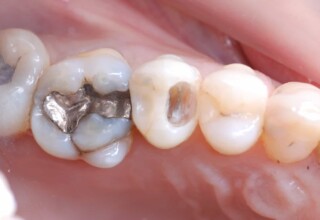

Αποκατάσταση Οπίσθιου Απονευρωμένου Δοντιού με Ανασύσταση Σύνθετης Ρητίνης

Η συνήθης αποκατάσταση ενός απονευρωμένου οπισθίου δοντιού είναι με μια στεφάνη. Ο κύριος λόγος είναι η προληπτική προστασία από κάταγμα και την επακόλουθη εξαγωγή. Σε πολύ συγκεκριμένες περιπτώσεις όπου εξειδικευμένα κριτήρια (κυρίως η ποσότητα της εναπομείνουσας οδοντικής ουσίας) ικανοποιούνται ή όταν η οικονομική δυνατότητα του ασθενή το επιβάλει, μια εκτεταμένη ανασύσταση συνθέτης ρητίνης μπορεί ν’αποκαταστήσει την αισθητική και λειτουργικότητα του δοντιού.